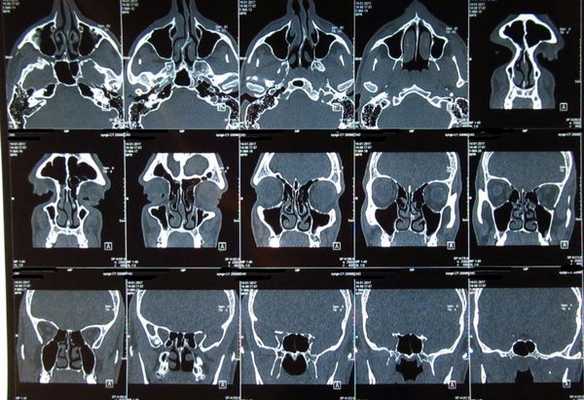

Тотальное заполнение жидкостью (кровью?) левой верхнечелюстной пазухи, повреждение носовой перегородки на компьютерной томограмме

КТ носовых пазух (фронтальный срез). Стрелками отмечено утолщение слизистых оболочек